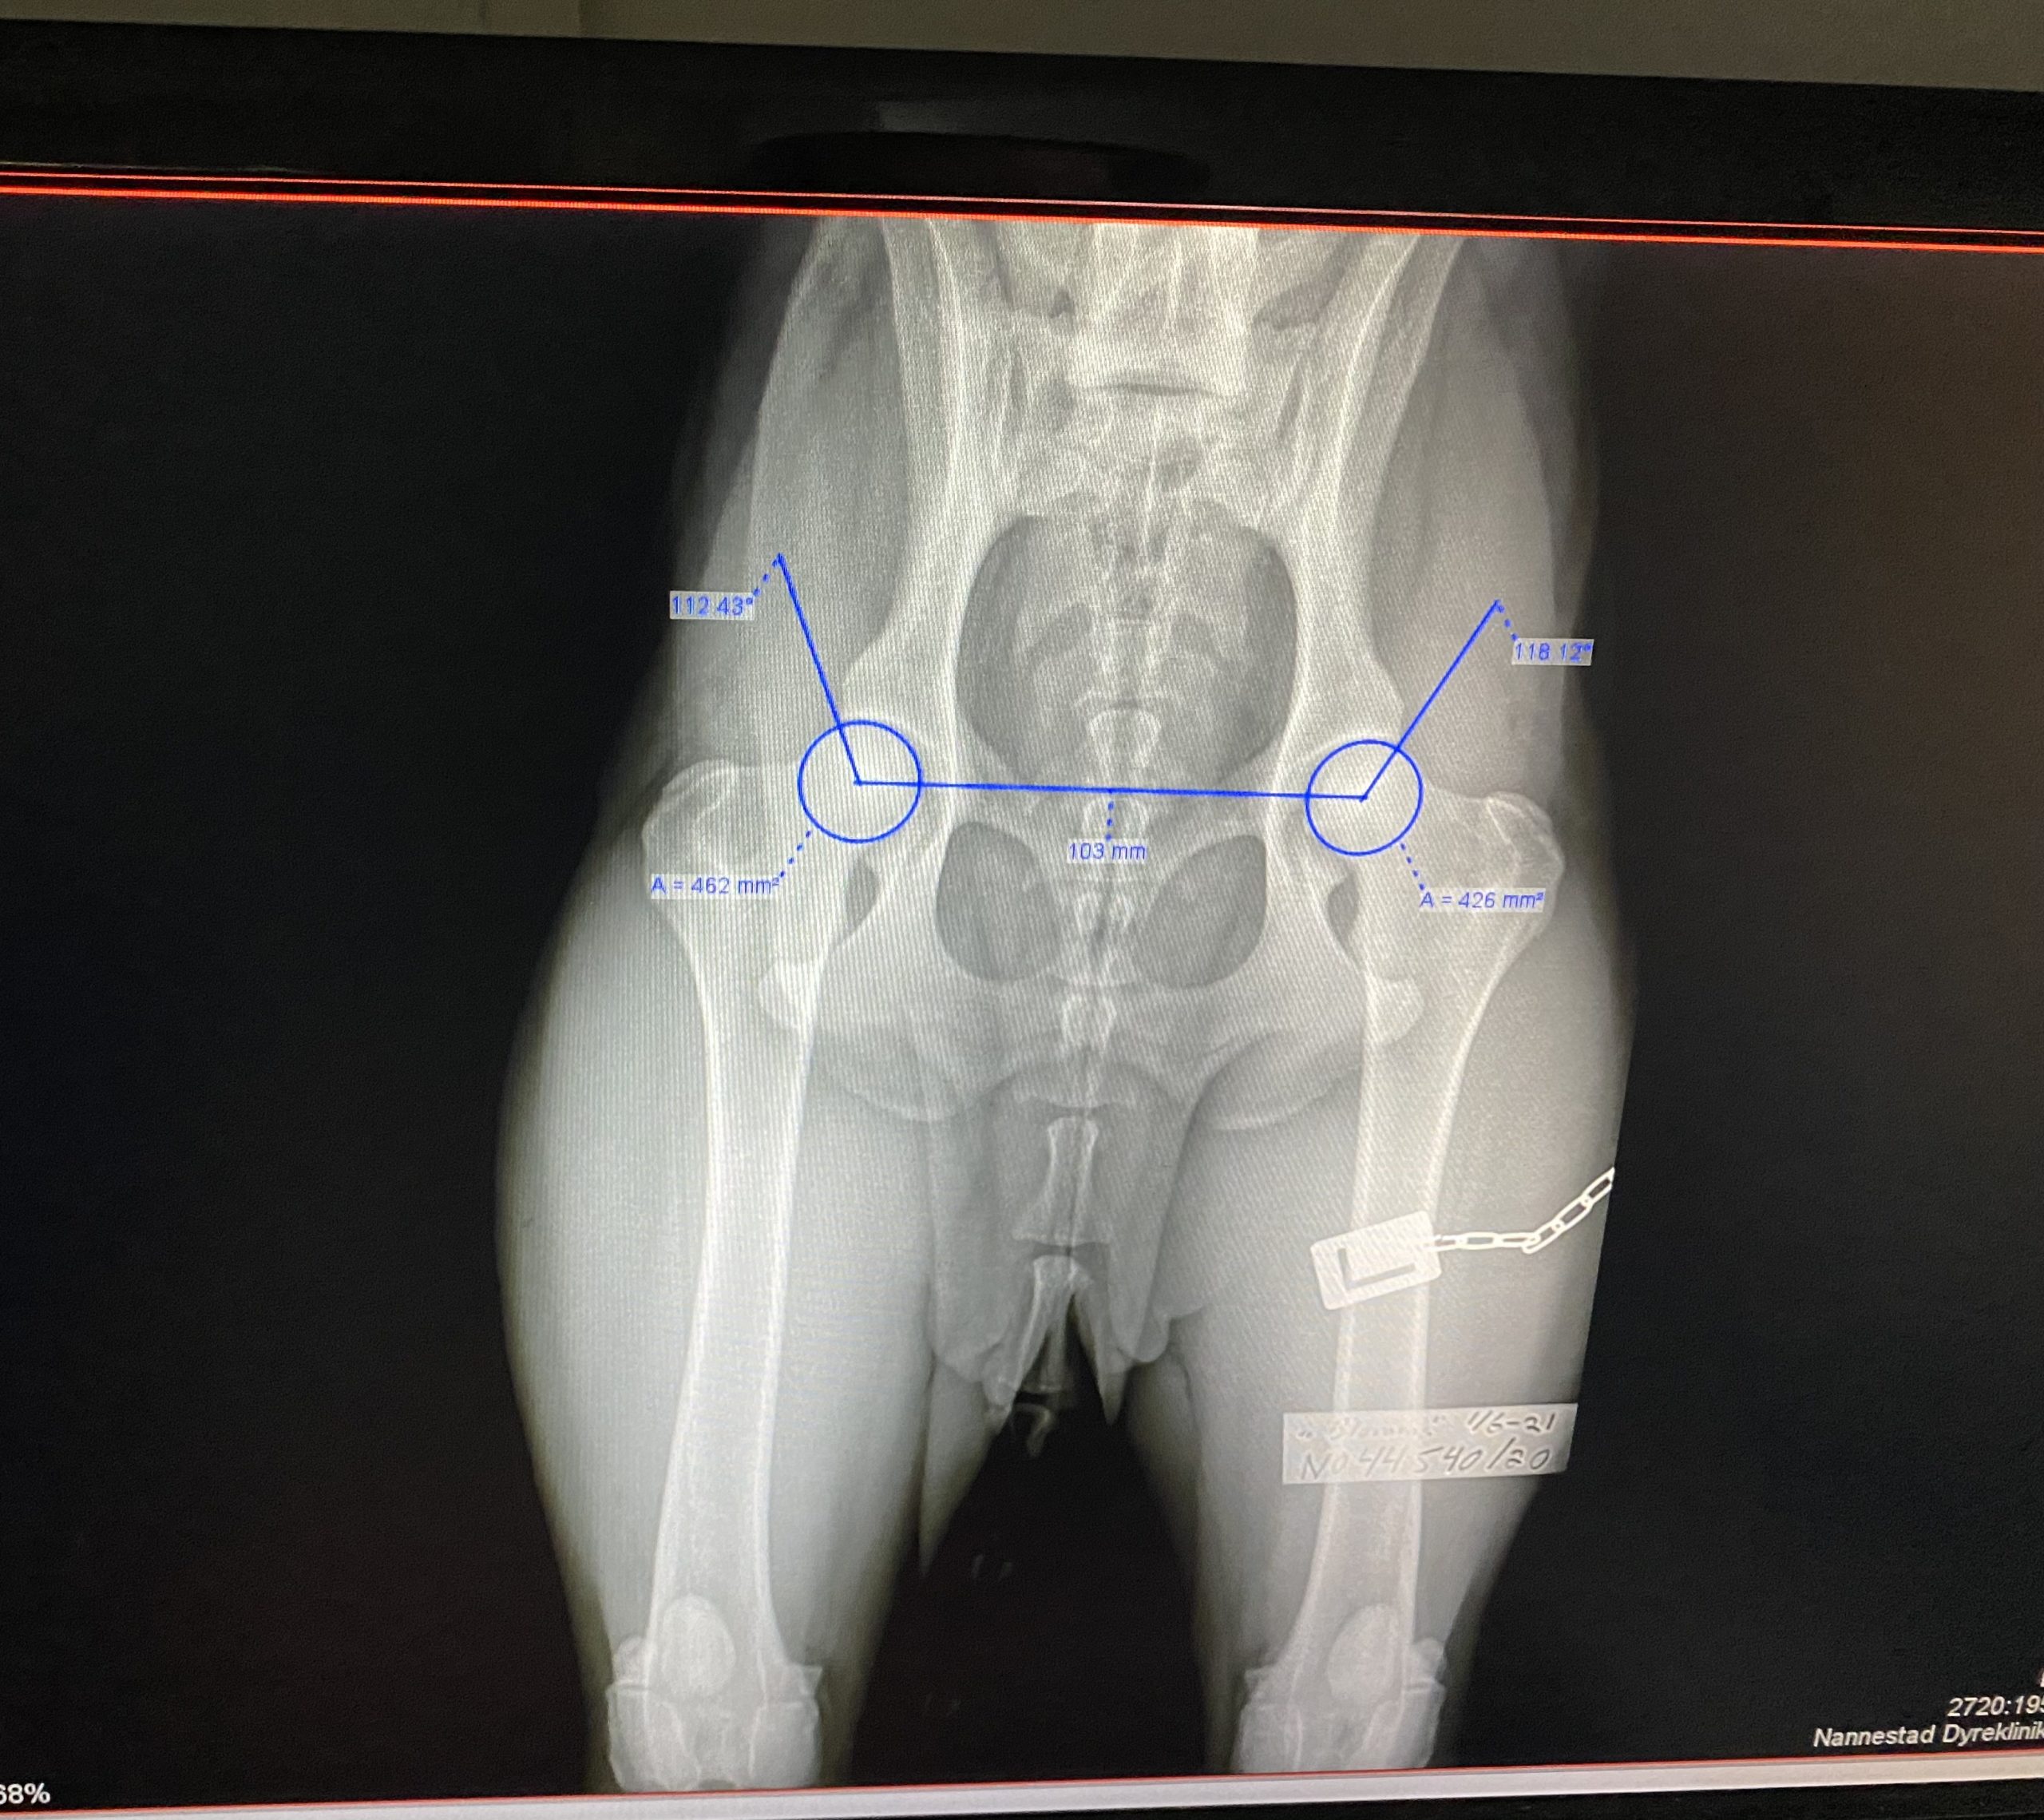

På K9 Nannestad Dyreklinikk tilbyr veterinærtjenester til smådyr. De har et særlig fokus på bruks- og jakthunder, og innehar høy kompetanse innen halthetsutredning, bildediagnostikk, kirurgi, kiropraktikk, samt forebygging og rehabilitering på sportshunder.